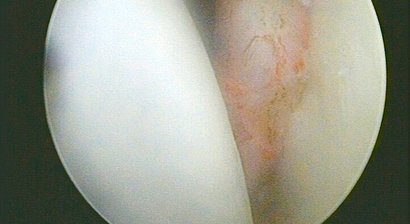

Knorpelschaden

Die Gelenkflächen des menschlichen Körpers bestehen aus hyalinem Knorpel. Dieser weist eine hohe Druckelastizität auf und ist beim Erwachsenen frei von Gefäßen und Nerven. Die Ernährung der Zellen muss daher über Diffusion erfolgen, was beim Gelenkknorpel übe...